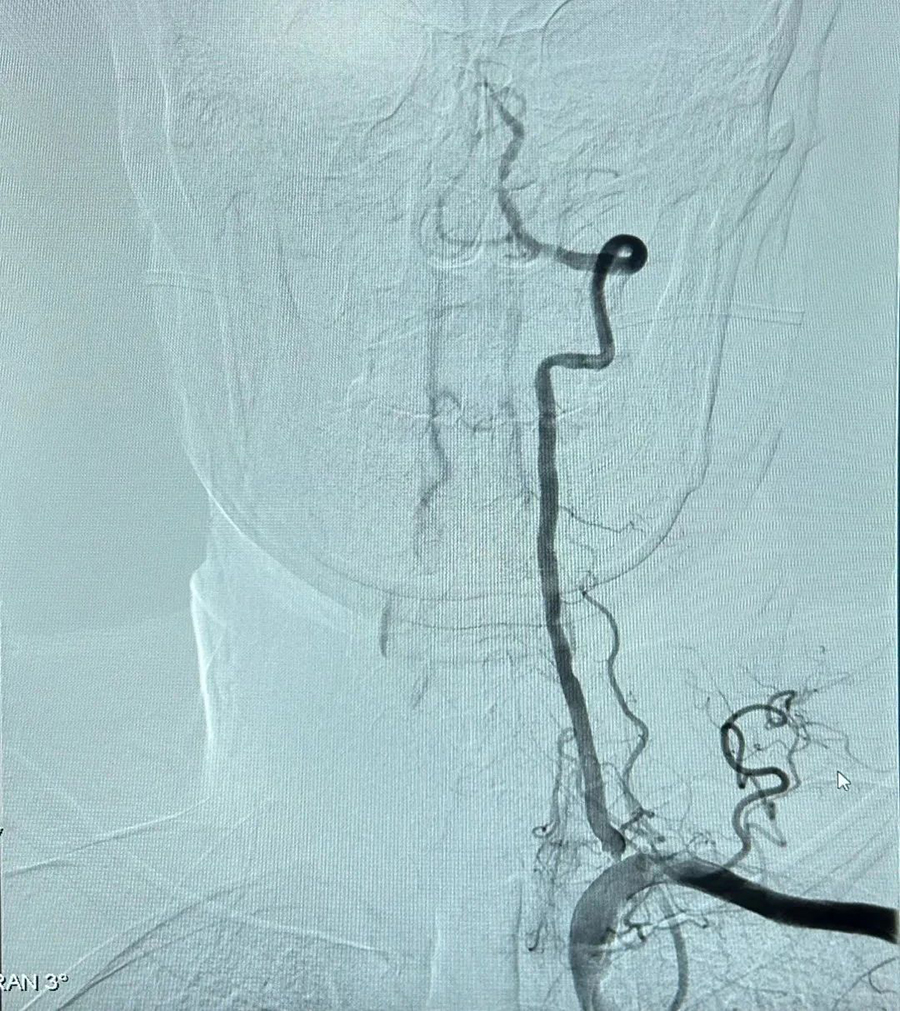

刻不容缓,神经内科立即请示副院长姜永飞,邀请介入科副主任医师张华会诊。专家们经过讨论评估,决定为刘先生行脑血管造影和脑血栓动脉溶栓治疗。这是一场与时间赛跑的治疗,大家沉着冷静,认真做着周密的术前准备,确保万无一失。

精湛技术 成功救治

手术过程顺利,随着溶栓药物的注射,刘先生的症状逐渐好转,在治疗结束时言语和肢体功能已经完全恢复正常。将刘先生安全送回病房后,护士长倪广艳带领护理团队为其及家属进行了脑卒中相关知识的健康宣教,确保刘先生能够保持健康的生活方式、避免脑卒中复发。